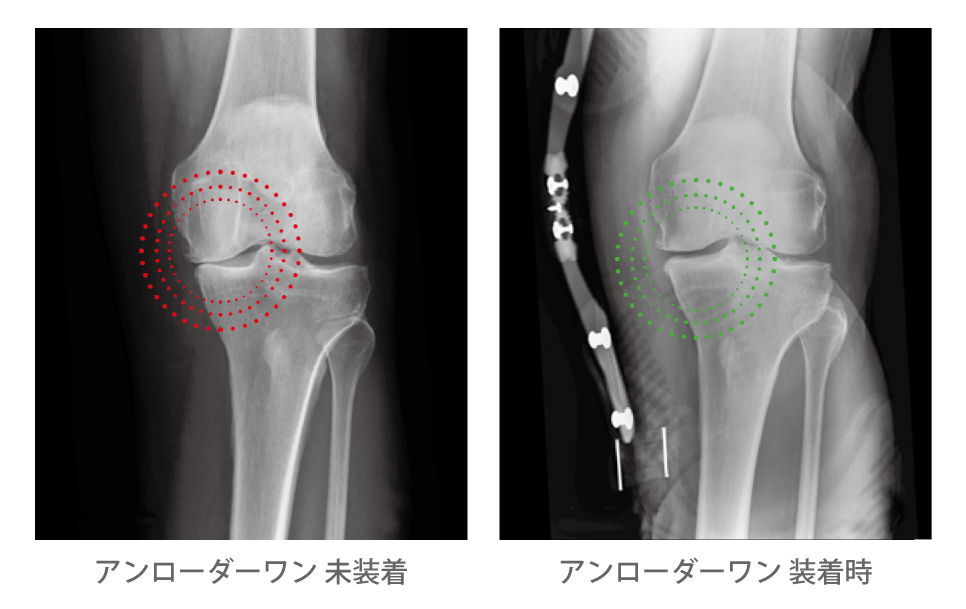

オズール社のアンローダーシリーズは、その名のとおり、矯正ではなく【Unloading=免荷】という概念で開発された膝装具です。膝関節の伸展に伴って、大腿部と下腿部に外反方向の応力(内側ヒンジ)が作用するため、膝関節表面の内側区画が免荷されます。免荷によって痛みが軽減し、患足への荷重量が増加し、連続歩行距離などの運動機能が向上した報告があります。

膝関節の影響を受けている側を 3-Point Leverage System(3点支持作用)を用いて免荷します。大腿とカフのシェルが2つの支点となり、Dynamic Force System™(DFS)ストラップが3つめのポイントとなります。このシステムが患部から圧を「解放」します。

アンローダーワン

簡単に装着でき、強力な免荷が得られます。膝に掛かる負担が大きい方、歩行時に感じる膝の痛みが高い方にお勧めします。